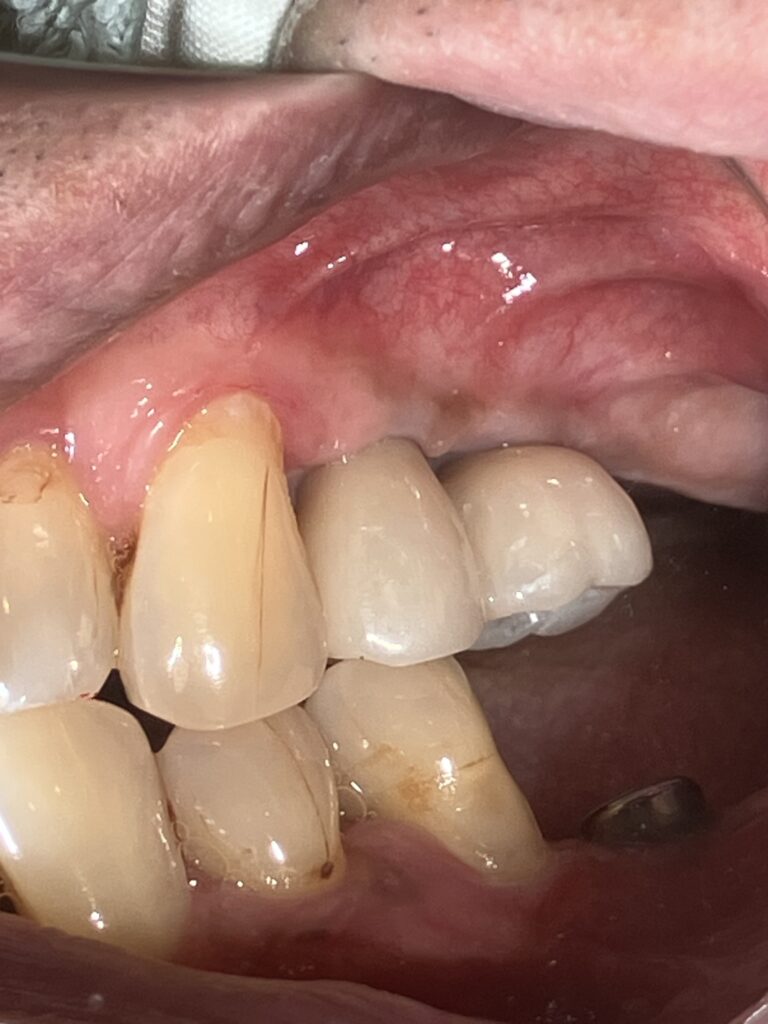

インプラントの上部構造の最終補綴物にメタルボンドと呼ばれるセラミックが使用されていました。今でも使用しますが1番の欠点として破折の可能性があることです。近年、物性や神秘性が格段に向上したジルコニアが、第一選択上がるようになりました。

フルジルコニアクラウンは、歯科補綴の一種で、全てジルコニアというセラミック素材でできた被せ物(クラウン)のことです。従来の金属にセラミックを焼き付けたメタルボンドクラウンとは異なり、アレルギーの原因となりうる金属は使用しません。

- 自然な見た目: 近年、審美性の高いジルコニア素材が登場しており、天然歯に近い色調や透明感を再現できます。金属を使用しないため、歯茎の変色(メタルタトゥー)の心配もありません。